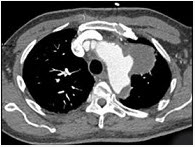

[单选题]患者男,50岁,胸背剧痛1周余,CT如图,最可能的诊断是A.主动脉弓真性动脉瘤B.主动脉弓假性动脉瘤C.主动脉弓夹层动脉瘤D.左上肺癌并侵犯主动脉弓部E.纵隔肿瘤